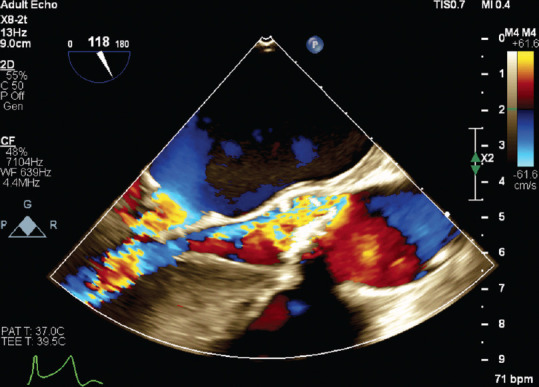

A Rare Case of Intramitral Valve Ring in the Setting of Shone Complex Diagnosed by Echocardiography.

一例通过超声心动图诊断出 Shone 复合物的罕见瓣膜内环。